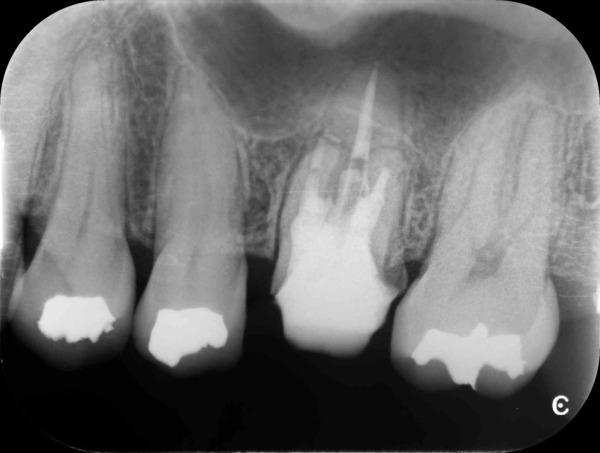

術前のデンタルX線写真と口腔内写真です。左下の一番奥の歯(#37)です。

診査の結果、神経は正常に生きていることが分かりました。その為、いきなり神経は取らずに虫歯を取り切った上で神経を温存する治療を進めていくこととなりました。

術後デンタルX線写真

この状態で1ヵ月から3か月ほど経過を診させていただき、神経に問題が起きないかどうか確認します。

3か月後のデンタルX線写真です。

神経も正常に生きており、レントゲン写真からも異常所見は認めません。